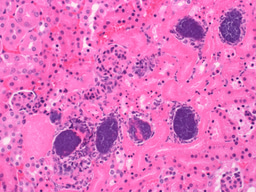

With these results in hand, we were curious as to whether we could use 6-TG as an antimicrobial, or anti-virulence compound, against S. aureus skin infection. Strikingly, physiologically relevant amounts of the pure compound significantly reduced skin damage caused by S. aureus. To elucidate the mechanism of action, we used RNA-seq to determine the changes that 6-TG was exerting on S. aureus and found that it exerts many effects on the pathogen. First, it blocks de novo purine biosynthesis, thereby preventing DNA replication and bacterial growth. Moreover, it reduces transcription from genes encoding for the global virulence regulator agr and for ribosome synthesis, resulting in a significant reduction in toxin production.